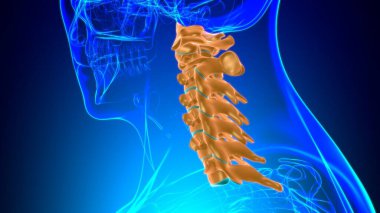

İnsan İskeleti Omurgası Servikal Omurga Anatomisi 3D İllüstrasyon

İnsanTıbbiparmakBoyunomurgaKalçaRADIUSsakralGöğüs kemiğiskapulaLeğen kemiğitorasikçene kemiğiparietallombersakrumTibiaUyluk kemiğiKöprücük kemiğisokumupazı kemiğidirsek kemiğioksipitaldiz kapağıkemikler3d oluşturmaGöğüs kafesiüst ekstremiteOmurga SütunuAyak bileği Ağrısıbel kemiğiayak kemikleriiskelet anatomisidiz eklem ağrısıservikal bölgeclavicle bonewrist carpalscervical vertebrae anatomyBenzer İçerikler